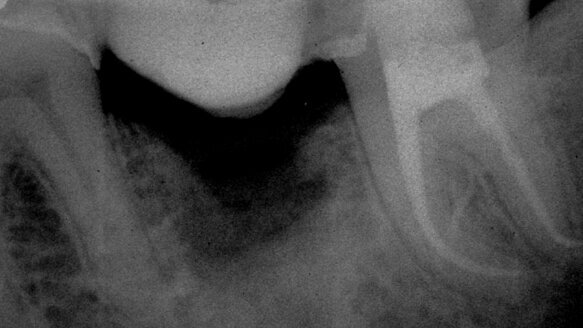

The best way to judge a system, in my opinion, is how effectively it shapes a canal without extraneous complications coming into play (Fig. 5–8).

We want to use a system that from the perspective of the canals we are shaping is most predictable in producing a shape of adequate dimensions, has minimal potential to distort the canal and no possibility of separating during its use. We cannot rely on a system that at times appears to be magnificent and at other times exacerbates our problems. The same system to be correctly designed must not only produce excellent results, but must do it consistently in all circumstances.

No one questions the fact that curved, narrow calcified canals will take more time to shape properly. However, at no time during the shaping of these challenging situations should we be exposed to systems that can add to the challenges by breaking.